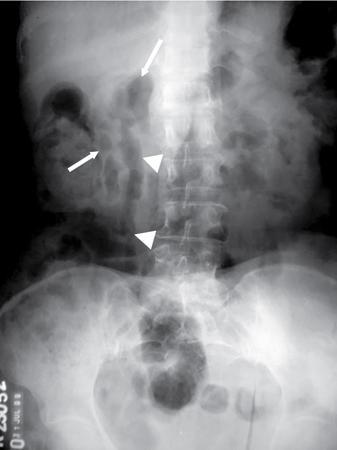

UNDERSTANDING THE ADULT ABDOMINAL RADIOGRAPH: TECHNIQUES AND INTERPRETATION Tanvi Modi Radiography of the abdomen is a common practice for the evaluation of abdominal organs. The anatomy and pathology of digestive, hepatobiliary and genitourinary systems can be assessed using radiographs, either as a stand-alone practice or as a primary imaging modality followed by contrast studies, ultrasound or cross-sectional imaging. In addition, abnormalities of the musculoskeletal or integumentary system can also be deduced on the basis of abdominal radiographs. This chapter intends to give an overview on the techniques and positioning in abdominal radiography as well as interpretation of normal and abnormal features. While superior imaging modalities such as ultrasound, computed tomography (CT), magnetic resonance imaging, capsule endoscopy and the likes have taken over abdominal imaging by and large, radiography still holds a pivotal role in certain situations and conditions, such as: The standard abdominal radiograph is taken in supine position and anteroposterior projection. This is also popularly known as the KUB (kidneys-ureters-bladder) radiograph. Previously, supine as well as erect radiographs were performed in all patients; however, this is not commonly done due to high-radiation dose. For all indications of abdominal radiography, including acute abdomen, supine radiographs are sufficient in terms of radiographic diagnosis, with the exception of perforation for which an erect chest or lateral decubitus radiograph can be performed if there is clinical suspicion. Patient should lie supine on the imaging table with median sagittal plane at right angles to the table and coincident with the midline of the table (Fig. 7.1.1.1). The body is divided into equal right and left halves by the median sagittal which passes through the sagittal suture of the skull. Pelvis should be adjusted so that the anterior superior iliac spines are equidistant from the table top. Gonadal shields, in the case of male patients, should be placed with the upper edge of the shield at the level of pubic symphysis. Although rarely used for female patients, these should be positioned between the anterior superior iliac spines and the pubic symphysis. The centre point of the image receptor should be approximately located at a point 1 cm below the line joining the iliac crests. The X-ray beam should be in a vertical direction, perpendicular to the table top and image receptor at the centre point. Collimation should be such that the soft tissue and subcutaneous region along lateral aspects of the abdominal cavity should be covered within the image. Also, the superior extent involving diaphragm and inferior extent involving the inferior pubic rami is important to look for any lower chest pathologies or any inguinal hernia. 35 × 43 cm (14 × 17 inches) in portrait orientation. On an average, abdominal radiograph exposes a patient to a dose of approximately 1.5 mSv, which is equivalent to 75 chest radiographs or 1/6th dose of a standard CT of the abdomen. The entrance skin dose is approximated to be 4 mGy. At such an effective dose, the additional lifetime risk of fatal cancer is 1 in 30,000. The exposure time is kept short. Patient is asked to exhale completely and hold their breath, with exposure taken at this point of full expiration to ensure imaging of abdominal organs in their natural positions. Modifications of this technique can be made depending on patient habitus and clinical condition. Kilovoltage peak (kVp) should be set to allow adequate visualization of abdominal soft tissue structures as well as semiopaque renal and biliary calculi. Average kVp is set at 70–85 kV. 102 cm (40 inches) Grids are commonly used to reduce scatter radiation. Placement of side marker on the image receptor at the time of radiographic exposure is essential. Bowel pattern depiction should be such that there is minimal lack of sharpness. Standard guidelines for abdominal radiography dictate that the radiograph should extend from the diaphragm up to the level of inferior pubic rami and must include the lateral abdominal wall musculature. The abdomen is divided into four quadrants on the basis of two perpendicular lines (Fig. 7.1.1.7). The vertical line passes through the mid sagittal plane and crosses the umbilicus and symphysis pubis. The horizontal line is a transverse line across the umbilicus at 90 degrees to the vertical line and is situated at the level of L4–L5 intervertebral disc. The quadrants are as follows: Another division system is dividing the abdominopelvic cavity into nine regions using two vertical and two horizontal planes (Fig. 7.1.1.8). The vertical planes, also known as the right and left lateral planes, are parallel to the midsagittal plane between midline and anterosuperior iliac spines on either side. Of the two horizontal planes, the upper transpyloric plane is at the level of lower border of L1 and the lower transtubercular plane is at the level of L5. The nine regions are: On a standard radiograph, the exposure should be such that the stomach, bowel loops, outlines of liver, spleen, kidneys, psoas muscles should be well identified. Also, lumbar transverse processes should be seen. Arch of the pubic symphysis should be visible to evaluate bladder region. A well-centred film without rotation will demonstrate bilaterally symmetrical lower ribs, iliac wings, ischial spines and obturator foramina. Different structures seen on an abdominal radiograph can be classified into five basic densities: Identification of different structures depends on the relative degree of contrast between their densities. The demarcation is clearer in chest and is diminished in abdomen due to relative similar soft tissue density of various structures. On a normal radiograph, relatively large amounts of gas in stomach and colon with minimal small bowel gas can be seen. Further, colonic gas can vary from negligible to extensive, mimicking obstruction pattern; however, usually the gas is enough to delineate colonic haustral pattern. Faecal matter gives a mottled appearance to colonic gas. Short-air fluid levels on an erect radiograph may be seen even in normal cases. The normal appearance of small bowel loops on an abdominal radiograph follows the rule of threes: Stomach is seen in the left upper quadrant and is visualized when distended with air. It is commonly seen extending from T11 to L2 level. Common feature identifying the stomach is the fundal gas which is usually seen as an air fluid level within the gastric lumen. Small bowel loops are distributed to the centre of the abdominal cavity and large bowel loops are peripheral. Duodenum is predominantly situated in right upper quadrant. It extends to left upper quadrant in the region of duodenojejunal flexure. Jejunum occupies the left upper and lower quadrants and is easily identified due to the presence of thick, numerous, closely spaced valvulae conniventes (Fig. 7.1.1.9A). The ileum occupies both lower quadrants and extends into right upper quadrant. Ileum has few and less prominent valvulae as compared to jejunum (Fig. 7.1.1.9B). Ascending and descending colon are retroperitoneal and have relatively fixed positions along lateral aspect of the abdominal cavity on either side. Transverse and sigmoid colon, on the other hand, may have a variable position due to their mobility along mesocolon and redundant pattern. These can be identified with confidence on account of haustrations and faecal matter (Fig. 7.1.1.10). Haustrations are usually well seen in ascending and transverse colon and poorly delineated beyond splenic flexure. Caecum is in the right lower quadrant, though it may be mobile or pulled up. Rectal gas is usually seen in the midline at the level of pelvis and its presence rules out large bowel obstruction. All these positions may vary due to anatomical conditions such as malrotation or pathological conditions, for example volvulus. Liver, spleen and renal outlines cannot be completely traced with precision due to the overlap by bowel loops. On a frontal projection, the liver appears as a triangular structure occupying right and left hypochondrium and epigastric region. Occasionally, the right lobe may be seen extending lower than the right renal shadow. This is a normal variant known as Reidel’s lobe. Gall bladder is situated in the posterior and inferior region of the liver and any pathology of the gall bladder should be looked for in this region. On a lateral radiograph, the gall bladder is anterior to the midcoronal plane. This helps in distinguishing gall bladder calculi from renal calculi, which will be more posteriorly situated. Spleen is seen in left upper quadrant/left hypochondrium, flushed to left lower ribs and left hemidiaphragm. Pancreas is present in the epigastric region (right and left upper quadrants) and is usually not identified in the absence of a pathology. The kidneys are bean-shaped retroperitoneal organs which are seen on either side of the vertebral column and lateral to psoas muscles. Due to the presence of liver on the right side, this kidney is slightly lower in position as compared to its contralateral counterpart. The visualization of kidneys on radiographs is facilitated by the surrounding fatty capsule. Kidneys lie between T11–12 and L2 level, with left kidney 1 cm higher than the right. Psoas muscle shadow can be normally seen along lateral aspect of lumbar spine bilaterally and is mildly concave (Fig. 7.1.1.11). Abdominal wall muscles are not routinely assessed on radiography; however, inclusion of lateral abdominal wall (muscles as well as subcutaneous plane) is a must while performing radiography. The flank stripe or the properitoneal fat stripe is a fat density linear concavity seen along lateral abdominal wall (Fig. 7.1.1.11). It is bound by the paracolic gutters and air-filled ascending and descending colon. All the solid organs in the abdomen are identified due to the fat density outlining them. Distortion of these fat lines helps in identifying organomegaly or focal mass lesions. The dome of urinary bladder is outlined by fat, which aids in differentiating its density from other soft tissue structures of the pelvis. Not all calcifications seen on abdominal radiograph are abnormal. Some may depict age-related changes such as vascular calcifications involving abdominal aorta, pelvic vessels, splenic artery in the region of left upper quadrant. Within the pelvis, phleboliths may be seen and mistaken for urinary calculi. Assessment of lumbosacral spine, iliac bones and femoral heads can be made on the basis of plain radiography. Degenerative changes may be commonly seen. Lower ribs can also be evaluated for pathologies. Dilated small bowel loops with rounded soft tissue density in midline over umbilical region suggests obstruction secondary to umbilical hernia. Pneumoperitoneum must be looked for in all cases of acute abdomen. While erect chest and left lateral decubitus radiographs can detect even 1 mL of free air, there are multiple signs on supine radiograph to suggest this diagnosis, for example Rigler’s sign, falciform ligament sign, football sign (Figs. 7.1.1.24 and 7.1.1.25). Retroperitoneal perforation may demonstrate air outlining psoas muscles and retroperitoneal organs. Small amount of free air may persist in the abdominal cavity up to 3 weeks after surgery, although it usually resolves within a week. Clinical history is important in such cases. Air foci within the bowel wall may represent bowel ischaemia/strangulation. Linear gas patterns in right hypochondrium may be due to two causes, that is pneumobilia and pneumoporta. The former can be seen normally postbiliary surgery, sphincterotomy, ERCP or in the case of abnormal fistulous communication between bowel and biliary tree (Fig. 7.1.1.26A). Pneumoporta (Fig. 7.1.1.26B) is a red flag and warrants further investigation to look for conditions such as mesenteric ischaemia and toxic megacolon. Pneumobilia is more centrally located whereas air shadows in pneumoporta are seen reaching up to periphery of liver. Air foci over renal shadows (Fig. 7.1.1.27), gall bladder or pancreas, in the absence of recent procedural history, suggest fulminant infection and mandate urgent intervention. Central midline calcific foci between T9 and T12 vertebrae can be attributed to calcific pancreatitis (Fig. 7.1.1.28). In the left upper quadrant, areas of calcification seen involving a shrunken spleen may be seen in autosplenectomy. In right upper quadrant, calcified gall stones may be seen. These tend to be small, multiple, uniformly circumscribed and ring-like in appearance with central translucency (Fig. 7.1.1.29A). Mercedes Benz sign, a triradiate pattern of gas lucency, is associated with gallstones. In contrast, renal calculi are more commonly solitary, irregular, of homogenous density, conform to renal calyceal or pelvic outline (Fig. 7.1.1.29B) and are sometimes of staghorn configuration. On lateral view, the gall stones are more anteriorly located as compared to renal calculi, which may be partly superimposed on lumbar vertebrae. Ureteric calculi tend to overlap bony structures such as lumbar transverse processes (Fig. 7.1.1.29B) or sacroiliac joints. Extensive or patchy, curvilinear calcification of gall bladder wall is known as porcelain gall bladder which is often associated with malignant transformation. Calcification involving adrenal glands may be secondary to infection or haematoma, or a congenital condition known as Wolman’s disease where there is bilateral involvement. Discontinuous discrete midline tram track calcification in the abdomen may indicate atherosclerotic changes in abdominal aorta and branch vessels. However, when the calcification is in a globular pattern and seen below the level of L2 vertebra, aortic aneurysm should be suspected (Fig. 7.1.1.30). Appendicoliths, though not commonly seen, may sometimes be detected in right iliac region. Pelvic calcifications: vesical calculi, distal ureteric or vesicoureteric junction calculi, calcified fibroids, ovarian dermoid with tooth-like calcifications (Fig. 7.1.1.31) may be the cause of abdominal pain and should be diligently looked for. Vesical calculi are usually more large and central in location whereas calcification due to fibroids may be more lateral. Schistosomiasis is another cause of bladder wall calcification, as is calcification of bladder tumours. Phleboliths tend to be bilaterally symmetrical, with a lucent centre unlike ureteric calculi. While it is believed that phleboliths are located below the level of ischial spines and ureteric calculi above, this is not always true and should be confirmed with CT. Fluid may collect adjacent to properitoneal fat line, forming a linear soft tissue density separating the fat line from the ascending or descending colon. Hellmer’s sign demonstrates medial displacement of lateral edge of liver (hepatic angle), due to fluid collection or ascites. Gross ascites may appear as generalized abdominal haziness or diffuse increased density of pelvis. Abscesses can involve any solid organ and in such cases may be difficult to demonstrate on plain radiography alone. Enlargement of organ or faint gas densities within can be suggestive of the same. In the case of peritoneal abscess, mottled density due to air, fluid and necrotic contents point towards this diagnosis, especially in right iliac fossa in association with appendicitis. Retroperitoneal abscess, similar to any retroperitoneal mass, may cause displacement of retroperitoneal structures (Fig. 7.1.1.32). Subdiaphragmatic abscesses may show concomitant ipsilateral pleural effusion (Fig. 7.1.1.33). These should be differentiated from Chilaiditi syndrome. Fluid and soft tissue lesions present with the same density on radiographs. While it is difficult to characterize the lesion and organ of origin, clues for the same can be provided by organomegaly (Fig. 7.1.1.34), distortion of fat surrounding solid organs, displacement of bowel loops or solid organs. For example, a retroperitoneal lesion may cause anterior or inferior displacement of kidney, a pelvic mass may cause upward displacement of small bowel loops. Different densities such as fat or calcification may help in identifying organ of origin (e.g. fat and tooth densities seen in ovarian dermoid). Convexity of margins of psoas muscle on an abdominal radiograph can be due to haematoma, abscess or intramuscular tumour. Radiographs are performed for the initial diagnosis of foreign body in the abdomen including type, number of foreign bodies, location, size and shape (Fig. 7.1.1.35). Radiolucent foreign bodies such as wood, plastic, chicken bones will not be easily identified on radiography. Low kVp (65–70 kVp) can increase contrast and help identify these objects. In addition to an abdominal radiograph, chest radiography is also performed to exclude aspiration or oesophageal location of foreign body. Ingested or introduced foreign bodies may cause complications such as obstruction, perforation, fistula formation and sepsis. Hence, once their presence is confirmed, follow up radiography must be performed until they are eliminated. One must look for fractures/dislocation injuries involving the vertebrae or pelvic bones, especially after history of trauma. Lucent expansile lesions or sclerotic bony deposits which represent neoplasms, absent pedicle sign in cases of metastasis, metabolic bony changes such as rugger jersey appearance, Paget’s disease, arthropathies such as ankylosing spondylitis with bamboo spine appearance and sacroiliitis (Fig. 7.1.1.36) are some of the conditions which may be diagnosed based on an abdominal radiograph. Overlap of bowel loops over iliac blades may lead to a misdiagnosis of lucent lesions and should be evaluated with caution. Basal pneumonia may be the cause of acute abdominal pain and should be looked for in abdominal radiography. Similarly, pleural effusion, pericardial effusion, calcified pleural plaques, achalasia, interstitial fibrosis are few other findings that can be seen in lower chest on an abdominal radiograph. Basilar atelectasis can give a deceptive appearance of pneumoperitoneum (Fig. 7.1.1.37). Surgical clips, commonly in right hypochondrium after cholecystectomy, drainage tubes, ventriculoperitoneal shunts, femoral line catheters, IVC filters, stents (vascular, renal, biliary) (Fig. 7.1.1.38), stoma bags, contraceptive devices are some structures that may be seen in an abdominal radiograph. Correct knowledge of patient history and normal locations of these structures prevents misdiagnosis. Certain artefacts may be projected upon the radiograph due to surface structures such as trouser buttons, body piercing, sequins over clothing and should not be considered as a pathology. Multiple skin surface nodules in cases of neurofibromatosis, soft tissue focal swellings, such as abscesses, lipomas, haematomas, desmoid tumours and malignant lesions may be incidentally seen on radiography. These can be further evaluated using ultrasound or CT. Subcutaneous emphysema is another finding that may be seen in lower abdominal wall secondary to retroperitoneal perforation or diffusely along abdominal wall in the case of bowel perforation (Fig. 7.1.1.39). Foreign bodies such as bullets and pins may be seen lodged in abdominal wall. A systematic approach to abdominal radiographs is important for accurate diagnosis as follows: Despite the development of newer techniques for imaging of the abdomen, plain radiography still holds an important place in the initial assessment of acute abdomen. Positive and negative findings on an abdominal radiograph can direct further investigation. Ideal positioning, recognition of normal appearances and keen scrutiny for pathologies is a sine qua non for radiologists reading a plain film of the abdomen. OESOPHAGOGRAM Padma V. Badhe, Vikram Reddy, Sultan Moinuddin Shaukatali, Zillani Alam, Ravi Varma, Abhishek Bairy, Dasari Ravikiran, Revati Tekwani, Soniya Patankar, Megha Nair, Gautham Shankar Oesophagogram is the process of obtaining radiological images and simultaneous motion recording to evaluate function and disorders of pharynx, oesophagus and proximal stomach. Oesophagogram is usually done primarily to evaluate dysphagia. Some of the common indications are oesophageal motility disorders, strictures, gastro-oesophageal reflux disease (GERD) and suspected masses. It can also be used to detect uncommon anomalies like vascular rings/slings and aberrant anatomy. It also helps to evaluate further in cases where there is inability to pass upper GI scope. Double-contrast oesophagogram is mainly indicated in early mucosal disease like erosion, polyp, infection and tumours. If a motility disorder is suspected, dynamic technique (e.g. videofluoroscopy) is used for dysphagia or aspirations in cases of stroke, neuromuscular disorders, post head and neck surgery or radiation. Barium oesophagogram is contraindicated in suspected cases of perforation and tracheoesophageal fistula, aspiration, rarely if there is hypersensitivity to barium suspensions. It is also contraindicated in suspected oesophageal perforation where a water-soluble contrast agent is more suitable. However, ionic water-soluble contrast agent is better avoided in cases of aspiration or fistula with airway. The contrast examination of the pharynx is dangerous in cases of acute epiglottitis and must be ruled out on plain radiograph. An 80% w/v barium suspension is used in full column views. However, 200%–250% w/v barium suspensions is usually required for mucosal relief films. The barium sulphate mixture is fed to the patient either by spoon, by glass, or through a drinking straw, depending on its consistency. In videofluoroscopy, the pharyngeal phase of swallowing is usually safer with barium pudding than with thick barium and safer with thick barium than with thin barium. However, if the major abnormality is poor pharyngeal contraction leading to stasis in the piriform sinus (and epiglottic tilt is normal), a thin liquid is safer. Epiglottic motility is better assessed with thin barium because thick barium often obscures the epiglottic tip. Fluoroscopic equipment capable of cine fluoroscopy and capability for rapid sequence spot images (high frame rate) is needed for this examination, Barium suspension, straw, glass, Lead apron and radiation protective equipment. The patients are instructed to fast after midnight before the day of the examination. The pharynx should be made as dry as possible during the examination as high-density barium adheres to dry pharyngeal mucosa. Activities like smoking, chewing gum and lozenges must be abstained before the procedure as they impair barium coating by increasing the salivary secretion. Regular oral medications must be taken with sips of water; however, insulin must be skipped on the morning of examination. The major principles of a good oesophagogram includes mucosal coating, distension and projection. A routine oesophagogram consists of screening of the oral, pharyngeal and oesophageal phases of swallowing, single and double-contrast examination of pharynx, single contrast, double-contrast and mucosal relief views of the oesophagus. In cases of dysphagia, the examination is tailored depending on whether the symptoms are either pharyngeal or oesophageal and initial fluoroscopic findings. If patients’ symptoms are suggestive of oral or pharyngeal disorder then pharynx is evaluated first. Similarly, if patient is suspected to have thoracic oesophageal disease then, double-contrast examination of the oesophagus is performed before the pharyngeal evaluation. During an oesophagogram the positioning of the patient varies according to the type of examination (Table 7.1.2.1).